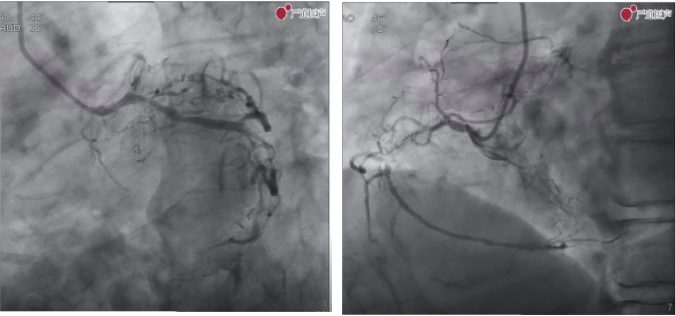

第一台手术直播患者为一名中年男性,主因反复胸痛呼吸困难2个月,加重1周入院。既往有高脂血症。术前超声LVEF55%,结构未见明显异常。2个月前外院造影LCX近中段次全闭塞,植入1枚支架,LAD近段弥漫病变,RCA起始部CTO,同时可以看到来自左冠的侧枝循环比较发达。

葛雷教授在术前讨论中提出,基于该病例的特点,可以先尝试正向开通,直接ADR,如果不成功再考虑逆向。令人意外的是,经过术前的几个月调养和药物治疗,手术直播时造影发现,该患者右冠闭塞消失,血流恢复,考虑右冠血栓自溶。因此,本例手术只可当作B型病变进行处理。

由于此病例难度降低,葛雷教授术中未行复杂操作,按照常规PCI手术流程20分钟左右即成功完成手术。